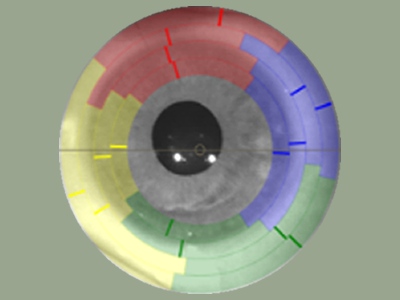

For established wearers, we would assess your current prescription and utilize anterior segment OCT to assess the fit of your current lenses. We may also run aberrometry measurements to see if you would benefit from higher-order aberration correction. We would determine if your current lens design is appropriate healthwise, or if you would benefit from a different lens design.

Best for those looking for the sharpest vision possible. Reduce or eliminate astigmatism, ghosting, haloes, glare, starbursts, and other visual disturbances (higher order aberrations). Can be combined with standard, custom, or ultra custom designed sclerals.

High definition optics to get rid of astigmatism, glare, ghosting, double vision, and other higher order aberrations (HOA)

Higher Order Aberration Correction (Ovitz xWave)

For those looking for the sharpest vision possible. Using Ovitz xwave technology, we can correct for ghosting, glare, haloes, starbursts, astigmatism, and other visual noise.